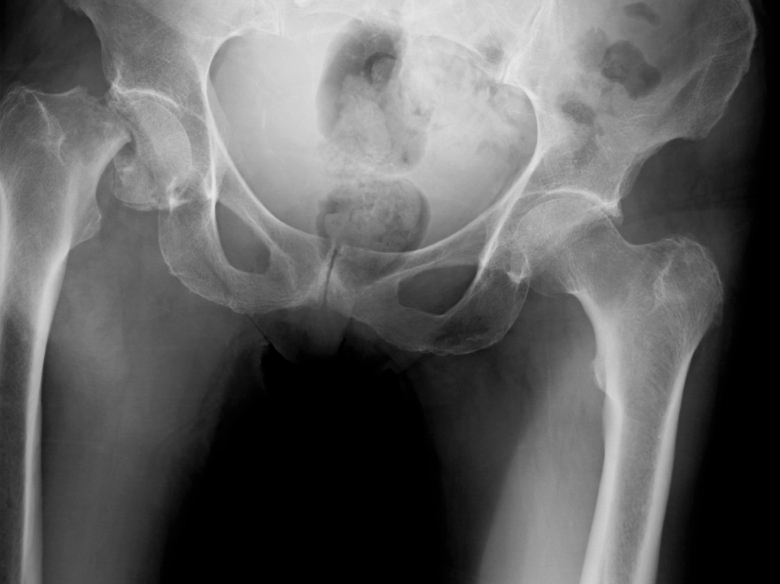

A broken hip like the one at left is a big health worry for older women.

Fractures are a serious health concern for people with osteoporosis. An old person with a broken hip is four times more likely to die within three months, because immobility can lead to pneumonia and other life-threatening infections.

Bone density is usually tested with a specialized X-ray machine that measures bone density in the hip and spine, commonly called a DEXA or DXA test. A scan costs about $200. Medicare pays for scans every two years, regardless of a person's bone density, and 22 percent of Medicare beneficiaries get a repeat scan within three years.